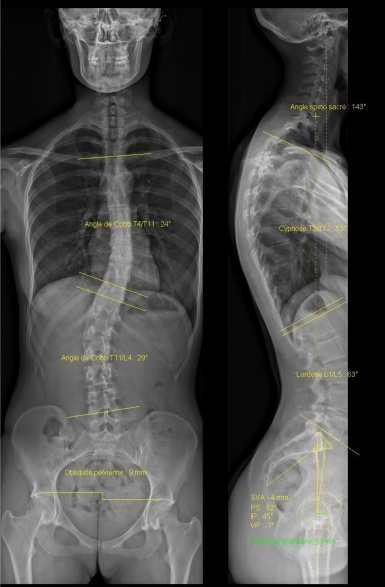

- l’étude d’un patient en position debout en obtenant des clichés simultanés de face et de profil du sommet de la tête jusqu’à la plante des pieds;

- l'analyse de la statique globale rachidienne et des membres inférieurs.

Ce système est actuellement la méthode de référence pour le diagnostic et le suivi des anomalies de la statique rachidienne (scolioses), surtout chez les jeunes chez qui il permet, au prix d’une exposition minime, une mesure automatisée des angles, avec une reproductibilité et une qualité d’images inégalées. Chez les personnes plus âgées, l’intégration de la statique du rachis à celle du corps entier constitue un avantage majeur.

Il permet aussi l’étude des membres inférieurs dans leur ensemble, certaines radiographies segmentaires, l’étude de la statique pelvienne.